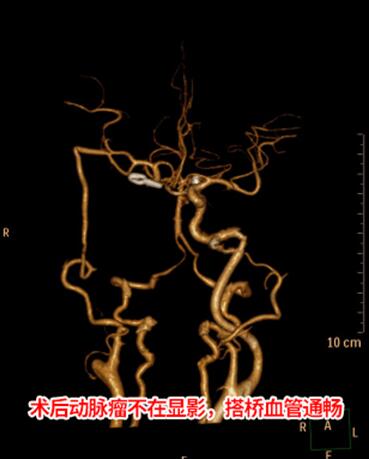

3组人员分工合作,从上午7时28分到下午14时40分,历7小时12分的手术,手术顺利完成,患者的这颗“炸弹”被成功拆除。术后病人恢复良好,未出现明显的肢体障碍,经过CT血管成像复查,动脉瘤不在显影,搭桥血管通畅,向颅内供血良好。胡女士的原先的头痛状况也消失了。术后,胡女士家人,为表达谢意,特意找了书法名家撰写了“杏林春暖”四个大字,送给神外三病区医疗团队。